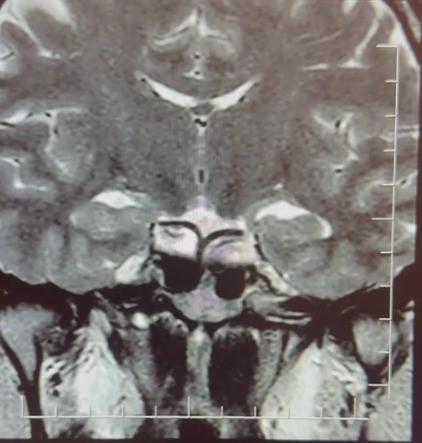

Yapılan ileri tetkiklerde hastaya hipofiz MR çekildiğini aktaran Çiftçoğlu, "MR sonucunda beynin hipofiz bölgesinde 'prolaktinoma' olarak adlandırılan bir tümör tespit ettik. Bu tümör, prolaktin hormonunun aşırı salgılanmasına neden oluyor. Genellikle iyi huylu olup ilaç tedavisiyle kontrol altına alınabiliyor" diye konuştu.

GEBELİK BELİRTİLERİ FARKLI HASTALIKLARIN HABERCİSİ ÇIKABİLİR Gebelik belirtilerine benzer şikayetlerin farklı hastalıkların habercisi olabileceğine dikkat çeken Çiftçoğlu, "Prolaktin hormonu aslında beyinde hipofiz bezinden salgılanan ve süt salınımını sağlayan hormondur. Bunun yüksek olduğunu tespit ettikten sonra hastada hipofiz MR çektirdik. Çektiğimiz beyin MR'ında hastanın hipofiz dediğimiz bölgede kitleyi tümörü tespit ettik. Prolaktinoma dediğimiz bir tümör. Prolaktinoma tümörü beyinde hipofiz bölgesinde bulunmakta olup prolaktin hormonunun aşırı miktarda salgılanmasını sağlayan bir tümördür. Bu durumda iyi huyludur, kanserleşme olmasını çok yoktur. Dolayısıyla ilaçla tedavisi mümkündür ama gebelik şikayetlerini de andırdığı için mutlaka ayırıcı tanıda akılda tutulması gereken bir durumdur. Hasta da bizle öğrendi 'hamileyim' diye geldi hasta, gebelik muayenesi olma talebiyle geldi ancak biz tümörü tespit ettik. Önce gebe olmadığını tespit ettik ve sonra 'Bu şikayetlere sebep olabilecek ne var?' diye araştırdığımızda bu durum ortaya çıktı. Yani tümörü de aynı gün içerisinde değil birkaç gün sonra ileri tetkik sayesinde öğrenmiş oldu" dedi.